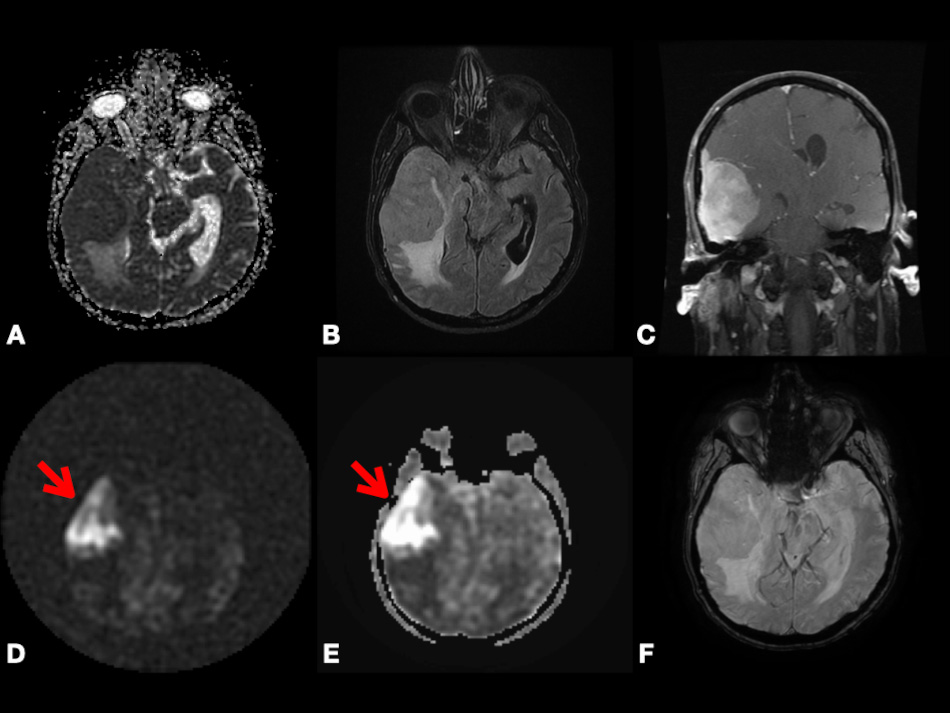

On DWI, Pavlisa et al. [94] found that ADCmean in SCs is significantly higher than both typical and atypical MGs. However, Ota et al. [74] found that there is no significant difference in ADC values between SCs versus MGs, PGs versus MGs, or SCs versus PGs. Thus, more clinical studies containing a large sample size are needed to evaluate the significance of DWI to differentiate between MGs and other extra-axial tumors. In Fig. 6, we present a case of right cerebral convexity atypical MG. The axial ADC map shows reduced diffusivity, while axial Pseudo-Continuous Arterial Spin Labeling (pcASL) source data and grayscale CBF map show marked heterogenous hyperperfusion. This demonstrates that MGs have high permeability and low diffusivity as mentioned in the literature. All of the previously mentioned studies differentiating between PG, SC, and MG using DCE, DSC, GRASP, and DWI are mentioned in Table 2 (Ref. [72, 73, 74, 76, 75, 88, 94]).

Fig. 6.Right cerebral convexity atypical meningioma (WHO Grade II). Axial ADC map (A), axial FLAIR (B), coronal fat-suppressed post-contrast T1-weighted (C), and axial SWI (F) images depicting large avidly enhancing plaque-like non-calcified mass with dural tail, reduced diffusivity, extensive vasogenic edema and mass effect with uncal herniation and ventricular trapping. Axial pcASL source data (D) and grayscale CBF map (E) depicting marked heterogenous hyperperfusion (red arrows). Abbreviations: ADC, Apparent diffusion coefficient; FLAIR, Fluid attenuated inversion recovery; SWI, Susceptibility weighted imaging; pcASL, Pseudo-Continuous Arterial Spin Labeling; CBF, cerebral blood flow.